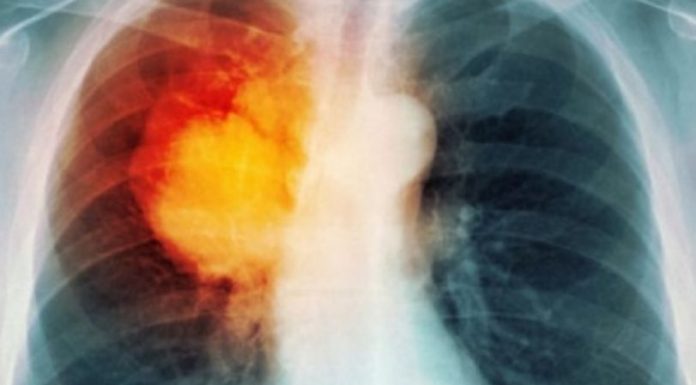

SPOK është termi që përfshin disa sëmundje të rënda të mushkërive, si bronkiti kronik, emfizema dhe gjendje të tjera që vështirësojnë funksionimin e mushkërive. Përveç duhanpirjes, faktorë të tjerë si ndotja e ajrit dhe gjenetika mund të kontribuojnë në zhvillimin e kësaj sëmundjeje.

Gratë janë më të rrezikuara se burrat që të kenë përkeqësim të gjendjes si pasojë e infeksioneve ose ekspozimit ndaj ndotësve të ajrit.